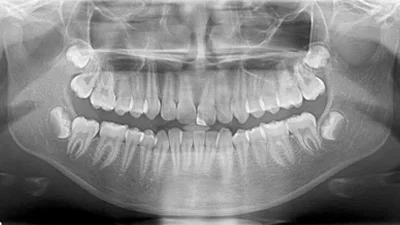

Panoramic dental X-ray of teeth, jawbones, and surrounding structures. Essential for dental and orthodontic planning.